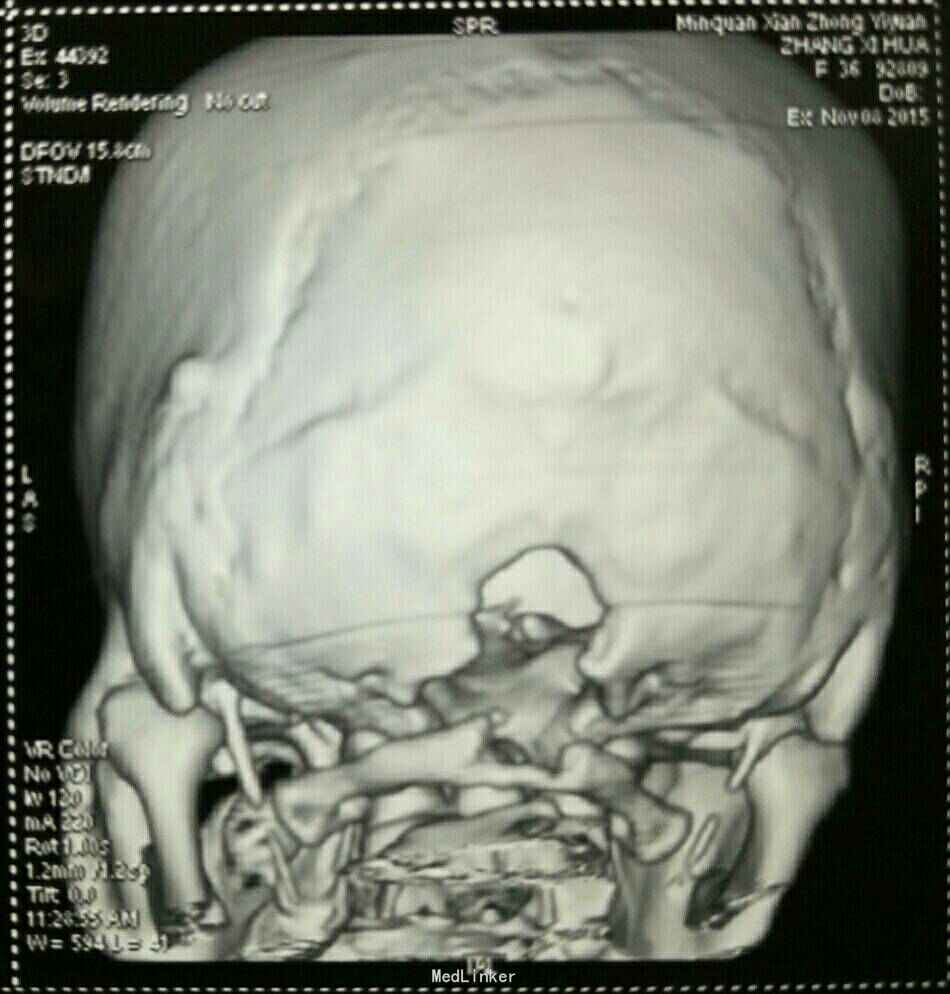

打开应用小脑扁桃体下疝并脊髓空洞症

小脑扁桃体下疝并脊髓空洞症

链接【小脑扁桃体下疝畸形】 又名阿诺德-奇阿(Arnold–Chiari)畸形,为常见的先天性发育异常。是由于胚胎发育异常使小脑扁桃体下部下降至枕骨大孔以下、颈椎管内,严重者部分延髓下段、四脑室下部下蚓部也下疝入椎管内。常合并有脊髓空洞,也可引起脑脊液循环受阻引起脑积水。小脑扁桃体下疝畸形常伴其他颅颈区畸形如脊髓脊膜膨出颈椎裂和小脑发育不全等。可表现为头痛、头面部上肢力弱、肩臂部痛温觉减退、吞咽困 难、眩晕、恶心、共济失调、甚至瘫痪等症状。 【治疗方法】